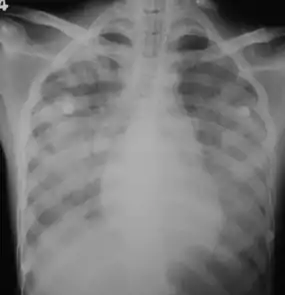

Imaging

In those who have lung involvement, a chest X-ray may demonstrate diffuse alveolar opacities.[13]